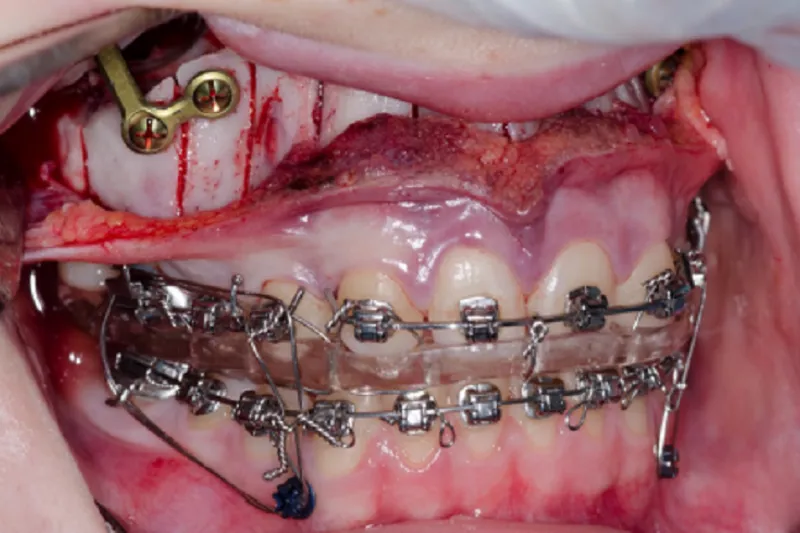

I forbindelse med kirurgien foretages kortikotomier af processus alveolaris samt lokal knogletransplantation med partikuleret knogle.